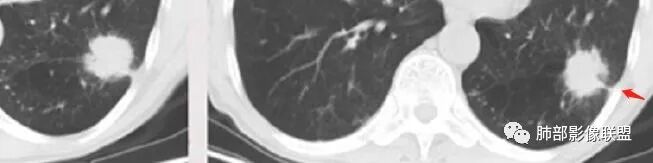

1.左侧分叶深一些

2.右侧糊墙

左侧胸膜凹陷

3.左侧支气管显示欠佳,似乎在门口堵塞

右侧支气管门口堵塞,有推移迹象

4.右侧坏死明显,内部囊变坏死边缘部分清楚、部分不清

左侧坏死不明显

虽然有一些平直凹陷边缘,但是也有棘状突起征

主要征象:病灶分叶不明显、较光整,局部胸膜栽赃,支气管门口堵塞,有推移迹象;增强后坏死明显,内部囊变坏死边缘部分清楚、部分不清楚,病灶内可见血管,局部稍毛糙,实性部分强化较明显,总体考虑恶性病变。一部分征象指向鳞癌(支气管截断、坏死较多,病灶内血管破坏),但又有肉瘤的一些特点(病灶较大,缺乏分叶,坏死边界清晰),要考虑到肉瘤样癌。

3、本病好发于60岁以上的老年男性,多数有吸烟史。周围型多于中央型,病灶边缘较清楚,多数光整圆钝,部分可见浅分叶,少数有毛刺,无胸膜凹陷征出现。CT平扫时呈软组织密度,较小的肿块密度较均匀,肿块较大时中央常出现坏死。增强扫描肿块多呈斑片状不均匀强化,而肿瘤周边厚薄不均的囊壁样强化较具特征性。周围型多数位于胸膜下,常常侵犯胸膜或胸壁。